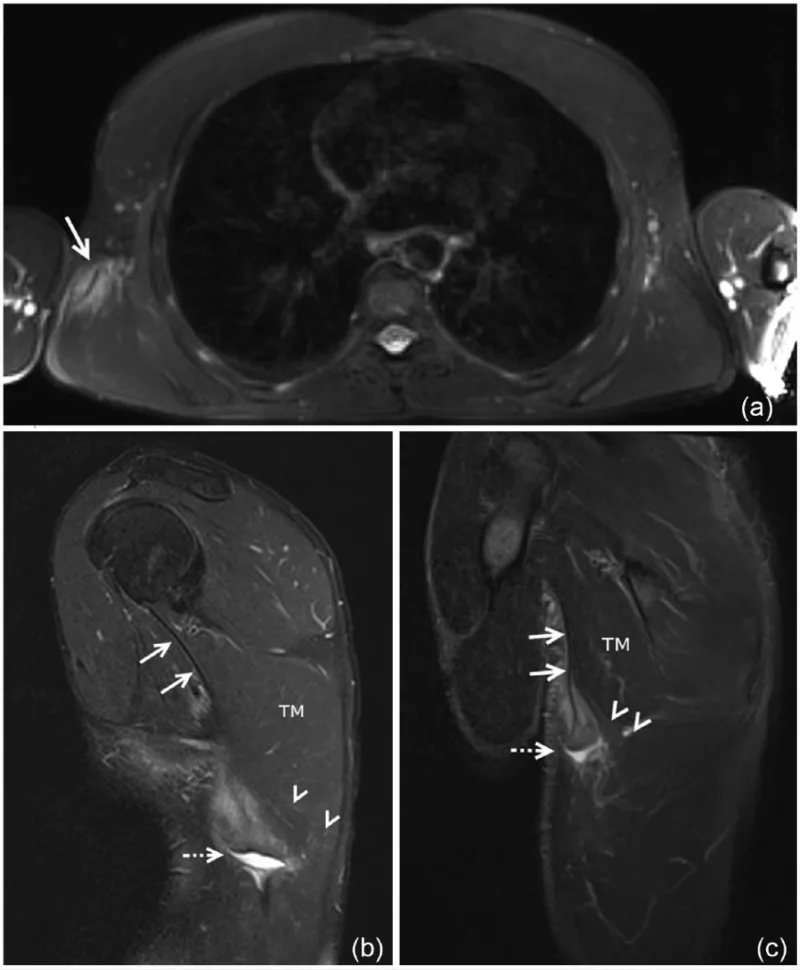

背中にある腫瘤に対して, 腫瘍が疑われてMRIを撮像したけど, よくわからなかったとのことで中高年患者さんが紹介されました.

広背筋腱は, 起始部では上腕骨の前内側部に付着しています(上図Aの2).

広背筋の腱や筋腱移行部で損傷があると, それに伴う出血で脇の下や背中に腫瘤を形成して, 腫瘍と間違われることがあります.

背中を診ると, 右の肩甲骨の下辺りの後外側に8 cmくらいの腫瘤を触知しました.

筋腱移行部(→)が白くなっていて, 背中に血腫(–→)を生じています.

持参したMRIを見たところ, 広背筋の中に出血して生じた血液の塊(血腫)があり, 筋肉内血腫と診断しました. 2週間前には痛みがあったそうですが, その後緩和して, 腫瘤も小さくなっているという臨床経過も一致. 患者さんに腫瘍ではなく, 出血による腫れで, 間もなく解消することを説明し, ご安心していただきました.